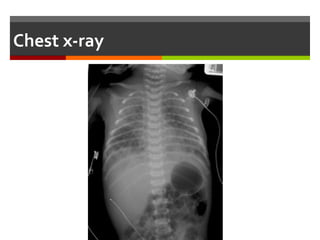

Chest x-ray :

 Prominent perihilar streaking (due to engorgement of

periarterial lymphatics)

 Fluid in the minor fissure

 Prominent pulmonary vascular markings

 Hyperinflation of the lungs, with depression of

diaphragm

 ► Chest x-ray usually shows evidence of clearing by 12-

18 hrs with complete resolution by 48-72 hrs

chest X-ray:TransientTachypnea of Newborn

Fluid in the

fissure